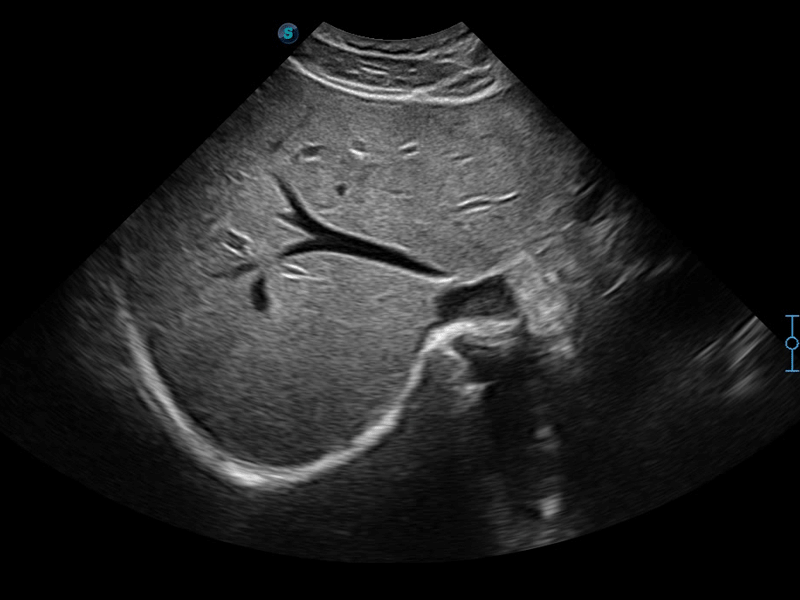

单晶体凸阵探头

凭借开立医疗先进的成像技术和优异的探头技术提供的清晰的图像表现,您可以更自信地做出临床决策。